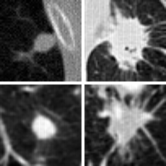

Our dataset We have collected CT scans (37% benign and 63% malignant) for this lung cancer diagnosis problem. The location for each pulmonary nodule is specified by the radiologist and each nodule was determined whether it is benign or malignant by taking a biopsy of the nodule. Compared to the LIDC-IDRI dataset, our dataset is even more challenging with more subtle differences between benign and malignant lung nodules as shown in Fig. 2.

![]() |

| (a) LIDC-IDRI | (b) Our dataset | ||